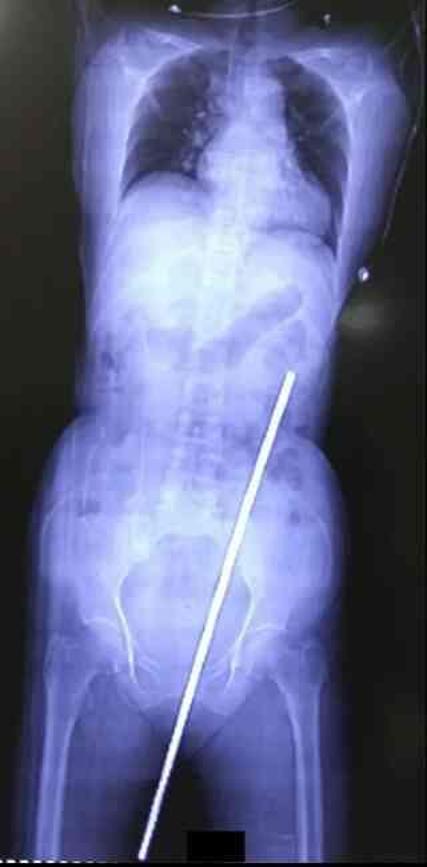

Hindistan'ın Manipal şehrinde 65 yaşındaki bir kadın, tarlada kayıp düşerek 60 cm uzunluğundaki paslı metal çubuğa saplandı. Tomografi görüntüleri, çubuğun kadının kalçasından girip karnına kadar ilerlediğini gösterdi.

Mucizevi bir şekilde, paslı ve gübreyle kaplı çubuk hiçbir hayati organa zarar vermedi. Kadın, komşusu tarafından hastaneye götürüldü ve daha sonra uzman bir merkeze nakledildi. Burada Kasturba Tıp Fakültesi'nden doktorlar tarafından muayene edildi.

Doktorlar, vakanın nadir olduğunu belirtti: "Nesne rektumu delip doğrudan retroperitona girdiği için, tüm ana iç organlar ve damar yapıları zarar görmedi. Bu, saplanma vakalarında çok nadir görülen bir durum."